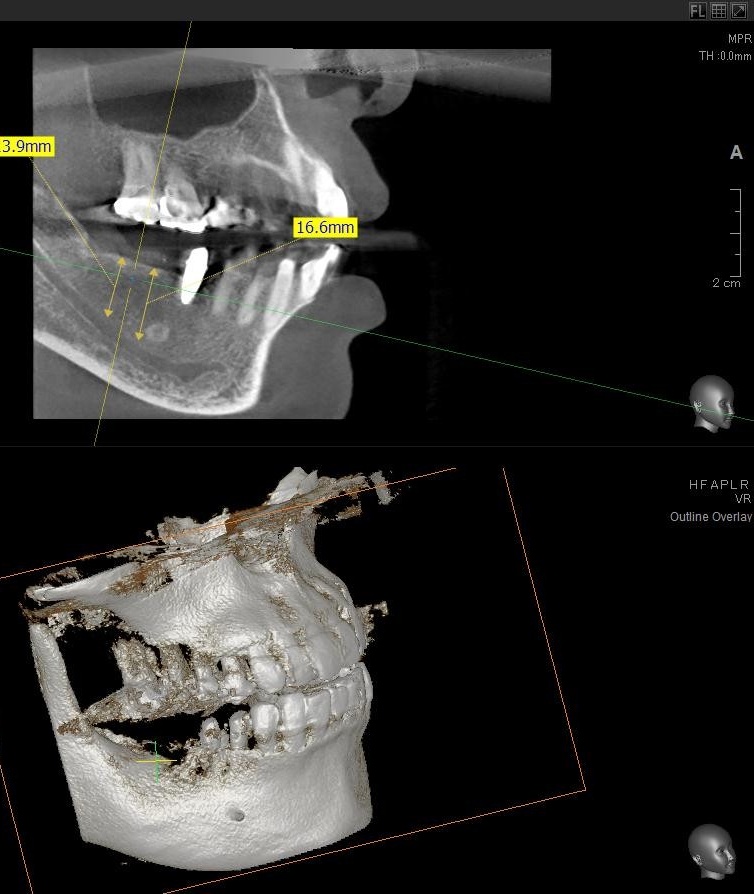

今回の患者様はインプラント植立を希望され、右下6番目・7番目の2本の植立が決まりました。

ドリルの先端を細い物から徐々に大きい物に変えながら、植立するインプラント体のネジの部分を除いた胴の部分の太さに合わせた大きさの穴を開けていきます。

開けた穴に、専用道具を使ってネジを締めるように長さ2センチ程のインプラントを骨に埋め込んでいきます。